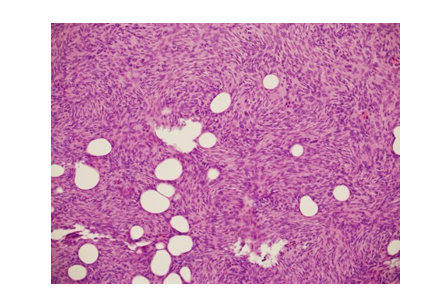

Pathologic examination of the excised mass revealed a relatively well-defined tumor nodule within the subcutaneous fat (Figure 3A and 3B). The proliferating tumor cells exhibited a uniform spindle cell morphology, with a prominent storiform growth pattern (Figure 4). There was no significant mitotic activity or necrosis. The tumor involved the fat (adipocytes) in a honeycomb-like pattern (Figure 4). Immunohistochemistry study revealed strong and diffuse positivity for CD34 marker in the tumor cells (Figure 5 and 6). S-100 marker was negative (which would argue against the potential histologic differential diagnosis of the rare and recently defined NTRK-rearranged spindle cell neoplasm (some cases of which can have a DFSP-like histologic features). No fibro sarcomatous transformation was noted.

Figure 4: The Proliferating Tumor Cells, Exhibiting a Uniform Spindle Cell Morphology, with a Storiform Growth Pattern, and Entrapment of Adipocytes in a Honeycomb-Like Pattern. (H&E Stain; Original Magnification 200x)